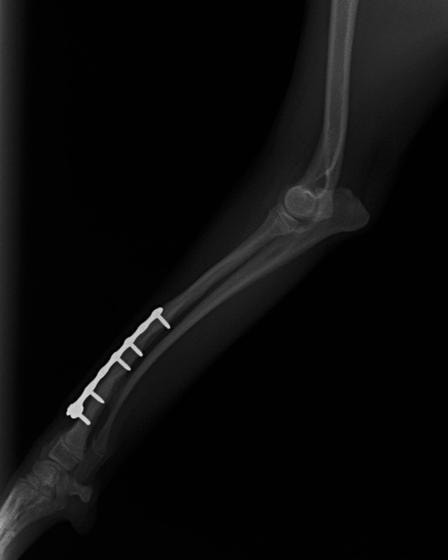

トイプードル 右遠位橈尺骨短斜骨折のALPSによる内固定

Locking Compression Plate

LCPは、スクリュー(ネジ)とプレート(金属の板)をロックする特殊な構造により骨折部位を固定する新しい世代のプレートシステムです。ひとつのホールでロッキングスクリューとスタンダードスクリューの使用を選択できるユニークな構造をしているため、骨折断端間の圧迫を目的とした従来型プレート固定法に加え、高い角度安定性を有するロッキングスクリューを用いた固定法の選択が可能です。従来のプレートシステムでは困難だった部分の骨折や癒合不全の症例に高い治療効果をもたらします。